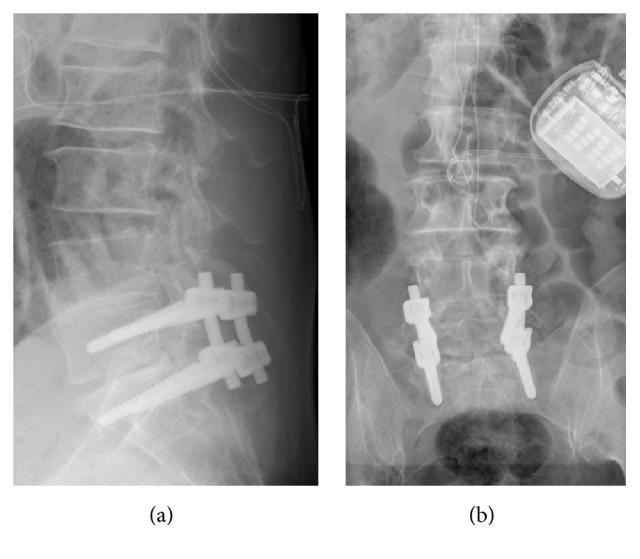

腰椎不稳和邻近节段病的病理解剖学危险因素:如何使用“顶端切除”?

Pathoanatomic Risk Factors for Instability and Adjacent Segment Disease in Lumbar Spine: How to Use Topping Off?

The goal of this review is to identify criteria indicating implantation of hybrid system into lumbar spine and to evaluate general benefits of use.

Predisposing factors for Adjacent Segment Disease (ASDi) are discussed in literature: laminar horizontalization, insufficiency of fascia thoracolumbalis, facet tropism, and facet sagittalization. Currently there is no evidence for topping off. There are only 12 studies and these have no consistent statements about use of a hybrid system for avoidance of ASDi.

CONCLUSION

Hybrid instrumentation of lumbar spine, either with pedicle-based technique or additional spacer, might possibly prevent ASDi from developing in previously damaged segment adjacent to a fusion. Good clinical data proving effectiveness of this new implant technique is as yet unavailable. Thus, currently one must speak of an unevaluated procedure. Various radiological classifications can assist in making a reliable decision as to whether hybrid instrumentation is an appropriate choice of therapy. Pathoanatomical conditions of facet joints and laminae as well as preservation of sagittal balance must also be considered.